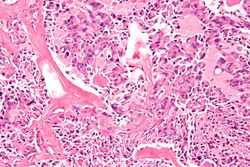

다발성 내분비종양증(MEN)은 두 가지 이상의 내분비 종양이 한 환자에게서 나타나는 유전 질환을 의미하며, MEN1, MEN2A, MEN2B, FMTC(가족성 수질 갑상선 암) 등의 유형으로 분류된다. MEN1은 베르머 증후군으로도 불리며, 췌장 종양, 뇌하수체 선종, 부갑상선 증식 등이 특징이다. MEN2A는 시플 증후군으로, 수질 갑상선 암, 갈색세포종, 부갑상선 과다형성이 나타난다. MEN2B는 바겐만-프로보에제 증후군으로, 점막 신경종, 마르판 유사 체형, 수질 갑상선 암, 갈색세포종 등이 특징이다. FMTC는 수질 갑상선 암의 한 종류이다. 이 질환들은 뇌하수체, 부갑상선, 췌장 등의 종양을 특징으로 하며, 각 유형별로 관련된 유전자와 증상이 다르다. 1903년부터 관련 사례가 보고되었으며, 1968년 "다발성 내분비 종양증"이라는 용어가 도입되었다.

MEN2A는 시플 증후군으로도 불린다.[34] 다발성 내분비종양증 2형(MEN2)의 한 종류이다.[29] MEN2A의 유병률은 1/40,000이다. 부갑상샘 과다형성(50%[26]), 갑상선수질암(100%[26]), 크롬친화세포종(>33%[26])과 관련이 있다. MEN2A는 RET 유전자와 관련이 있다.[29]2. 3. MEN2B (Wagenmann-Froboese 증후군)

MEN2B(바겐만-프로보에제 증후군)는 MEN 2형의 한 종류이다.[29] 1965년에 처음 언급되었다. 크롬친화세포종이 50%에서 발생하고,[26] 마르판 체형이 80%에서 나타난다.[26] 점막 신경종은 100% 발견된다.[26] 갑상선수질암은 85%에서 발생한다.[26] 유병률은 1,000,000명 중 1명(600,000명 중 1명[30] ~ 4,000,000명 중 1명[31]) 수준이다.[32] 원인이 되는 유전자는 RET ()이다.2. 4. FMTC (가족성 갑상선 수질암)

다발성 내분비 종양증 1형(MEN1)은 드문 유전성 내분비 암 증후군으로, 부갑상선 종양(95%), 내분비 위장관 췌장(GEP)관(30–80%), 전뇌하수체(15–90%) 종양이 특징이다.[19] 부신 피질 및 갑상선 종양, 내장 및 피부 지방종, 수막종, 안면 혈관섬유종 및 콜라게노마, 흉선, 위 및 기관지 유암종을 포함한 기타 내분비 및 비내분비 신생물도 발생한다. MEN1의 표현형은 20가지 이상의 다양한 내분비 및 비내분비 증상의 조합이 있을정도로 광범위하다.MEN1 환자는 일반적으로 MEN1의 가족력이 있으며, 상염색체 우성으로 유전되어 부모로부터 자녀에게 질병이 전염될 확률이 50%이다. MEN1 유전자 돌연변이는 환자의 70~95%에서 확인된다.[20]

MEN1 관련 내분비 종양은 다수가 양성이며 호르몬 과다 생성 또는 국소 종괴 효과로 증상을 유발하지만, 일부는 악성 종양 위험 증가와 관련이 있다. MEN1 환자의 약 3분의 1은 관련 암 또는 악성 종양으로 조기에 사망하며, 췌장 내분비 가스트리노마 및 흉선, 기관지 유암종이 주요 원인이다. 결과적으로 MEN1 환자의 평균 사망 연령은 남성 55.4세, 여성 46.8세로 일반 인구보다 현저히 낮다.